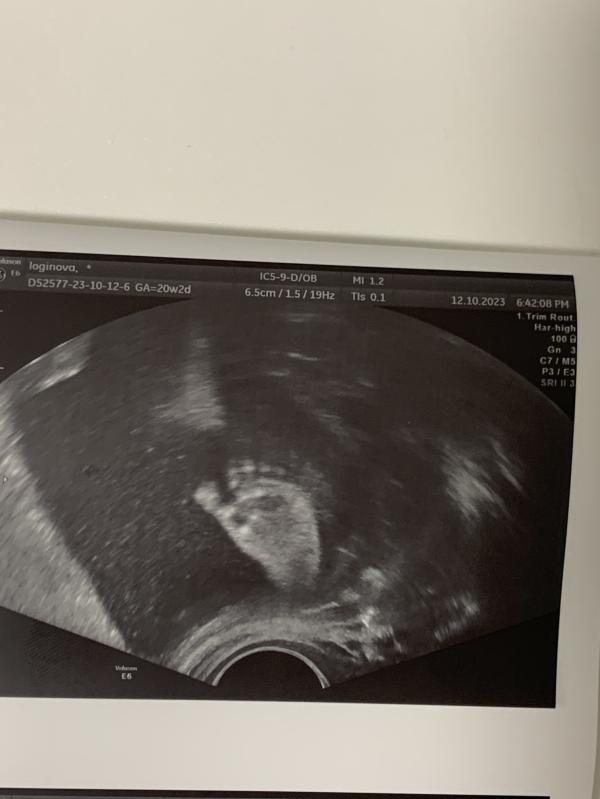

Второй скрининг прошёл, все хорошо 🥰

Прикреплю сюда фотку ножки 🦶❤️